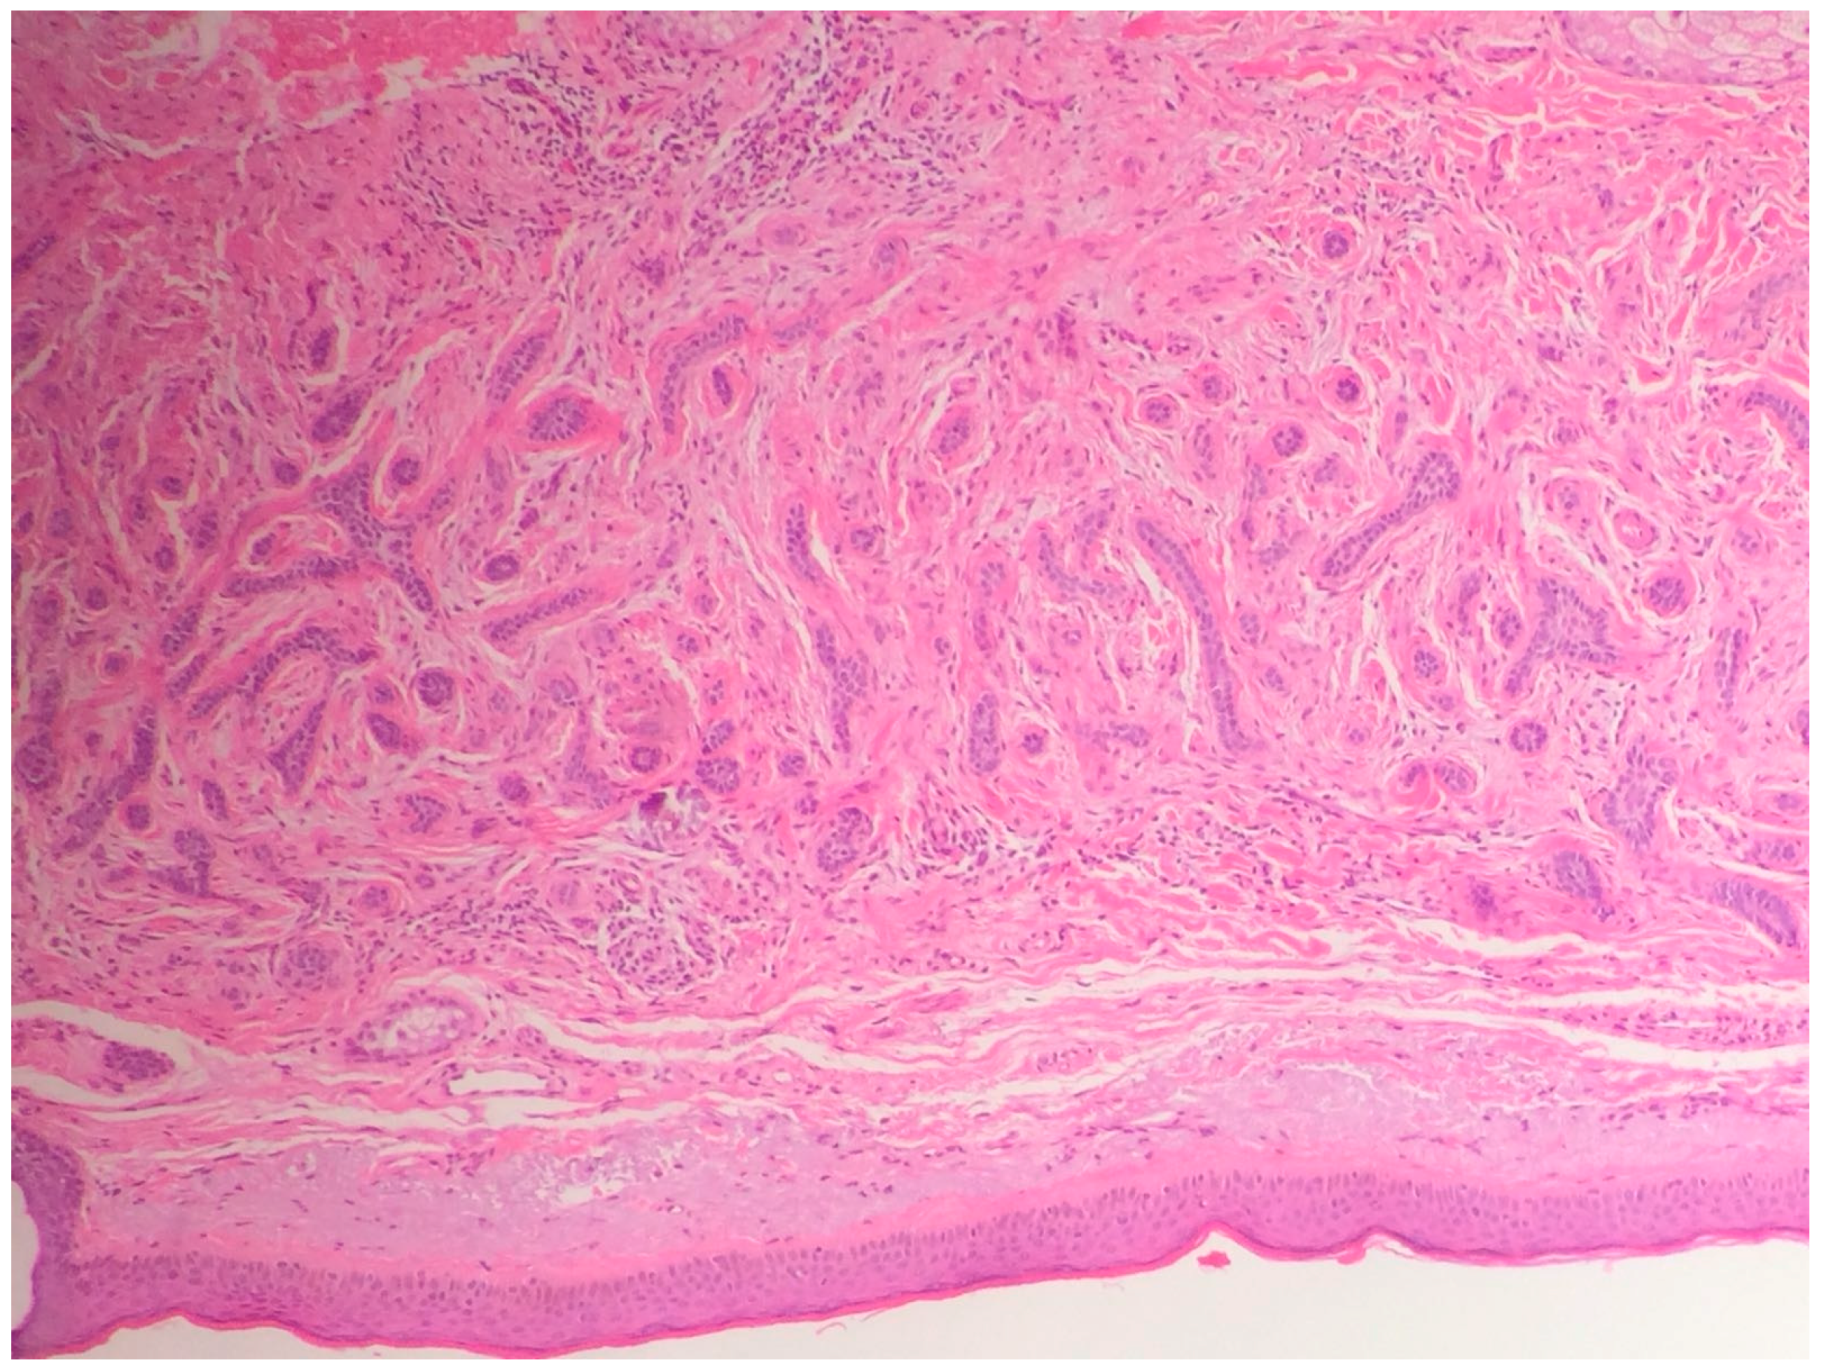

2.2. The Histologic Features of Actinic Keratosis, Bowen’s Disease, and Squamous Cell Carcinoma

2.2.3. Main Histologic Variant and Differential Diagnoses of NMSC with Squamous Differentiation